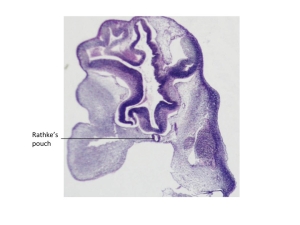

Stage 16

CfS 16

d29-30